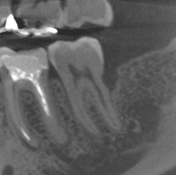

埋伏歯

-

70μm(Voxel Size)高精細モード搭載

End、根尖、破析、分岐部病変など精細読影をサポートします。

CT撮影時、Free FOVで撮影に必要な領域を絞り込み、

的確に高解像度70μmの世界トップレベルのCT画像を再現します。-